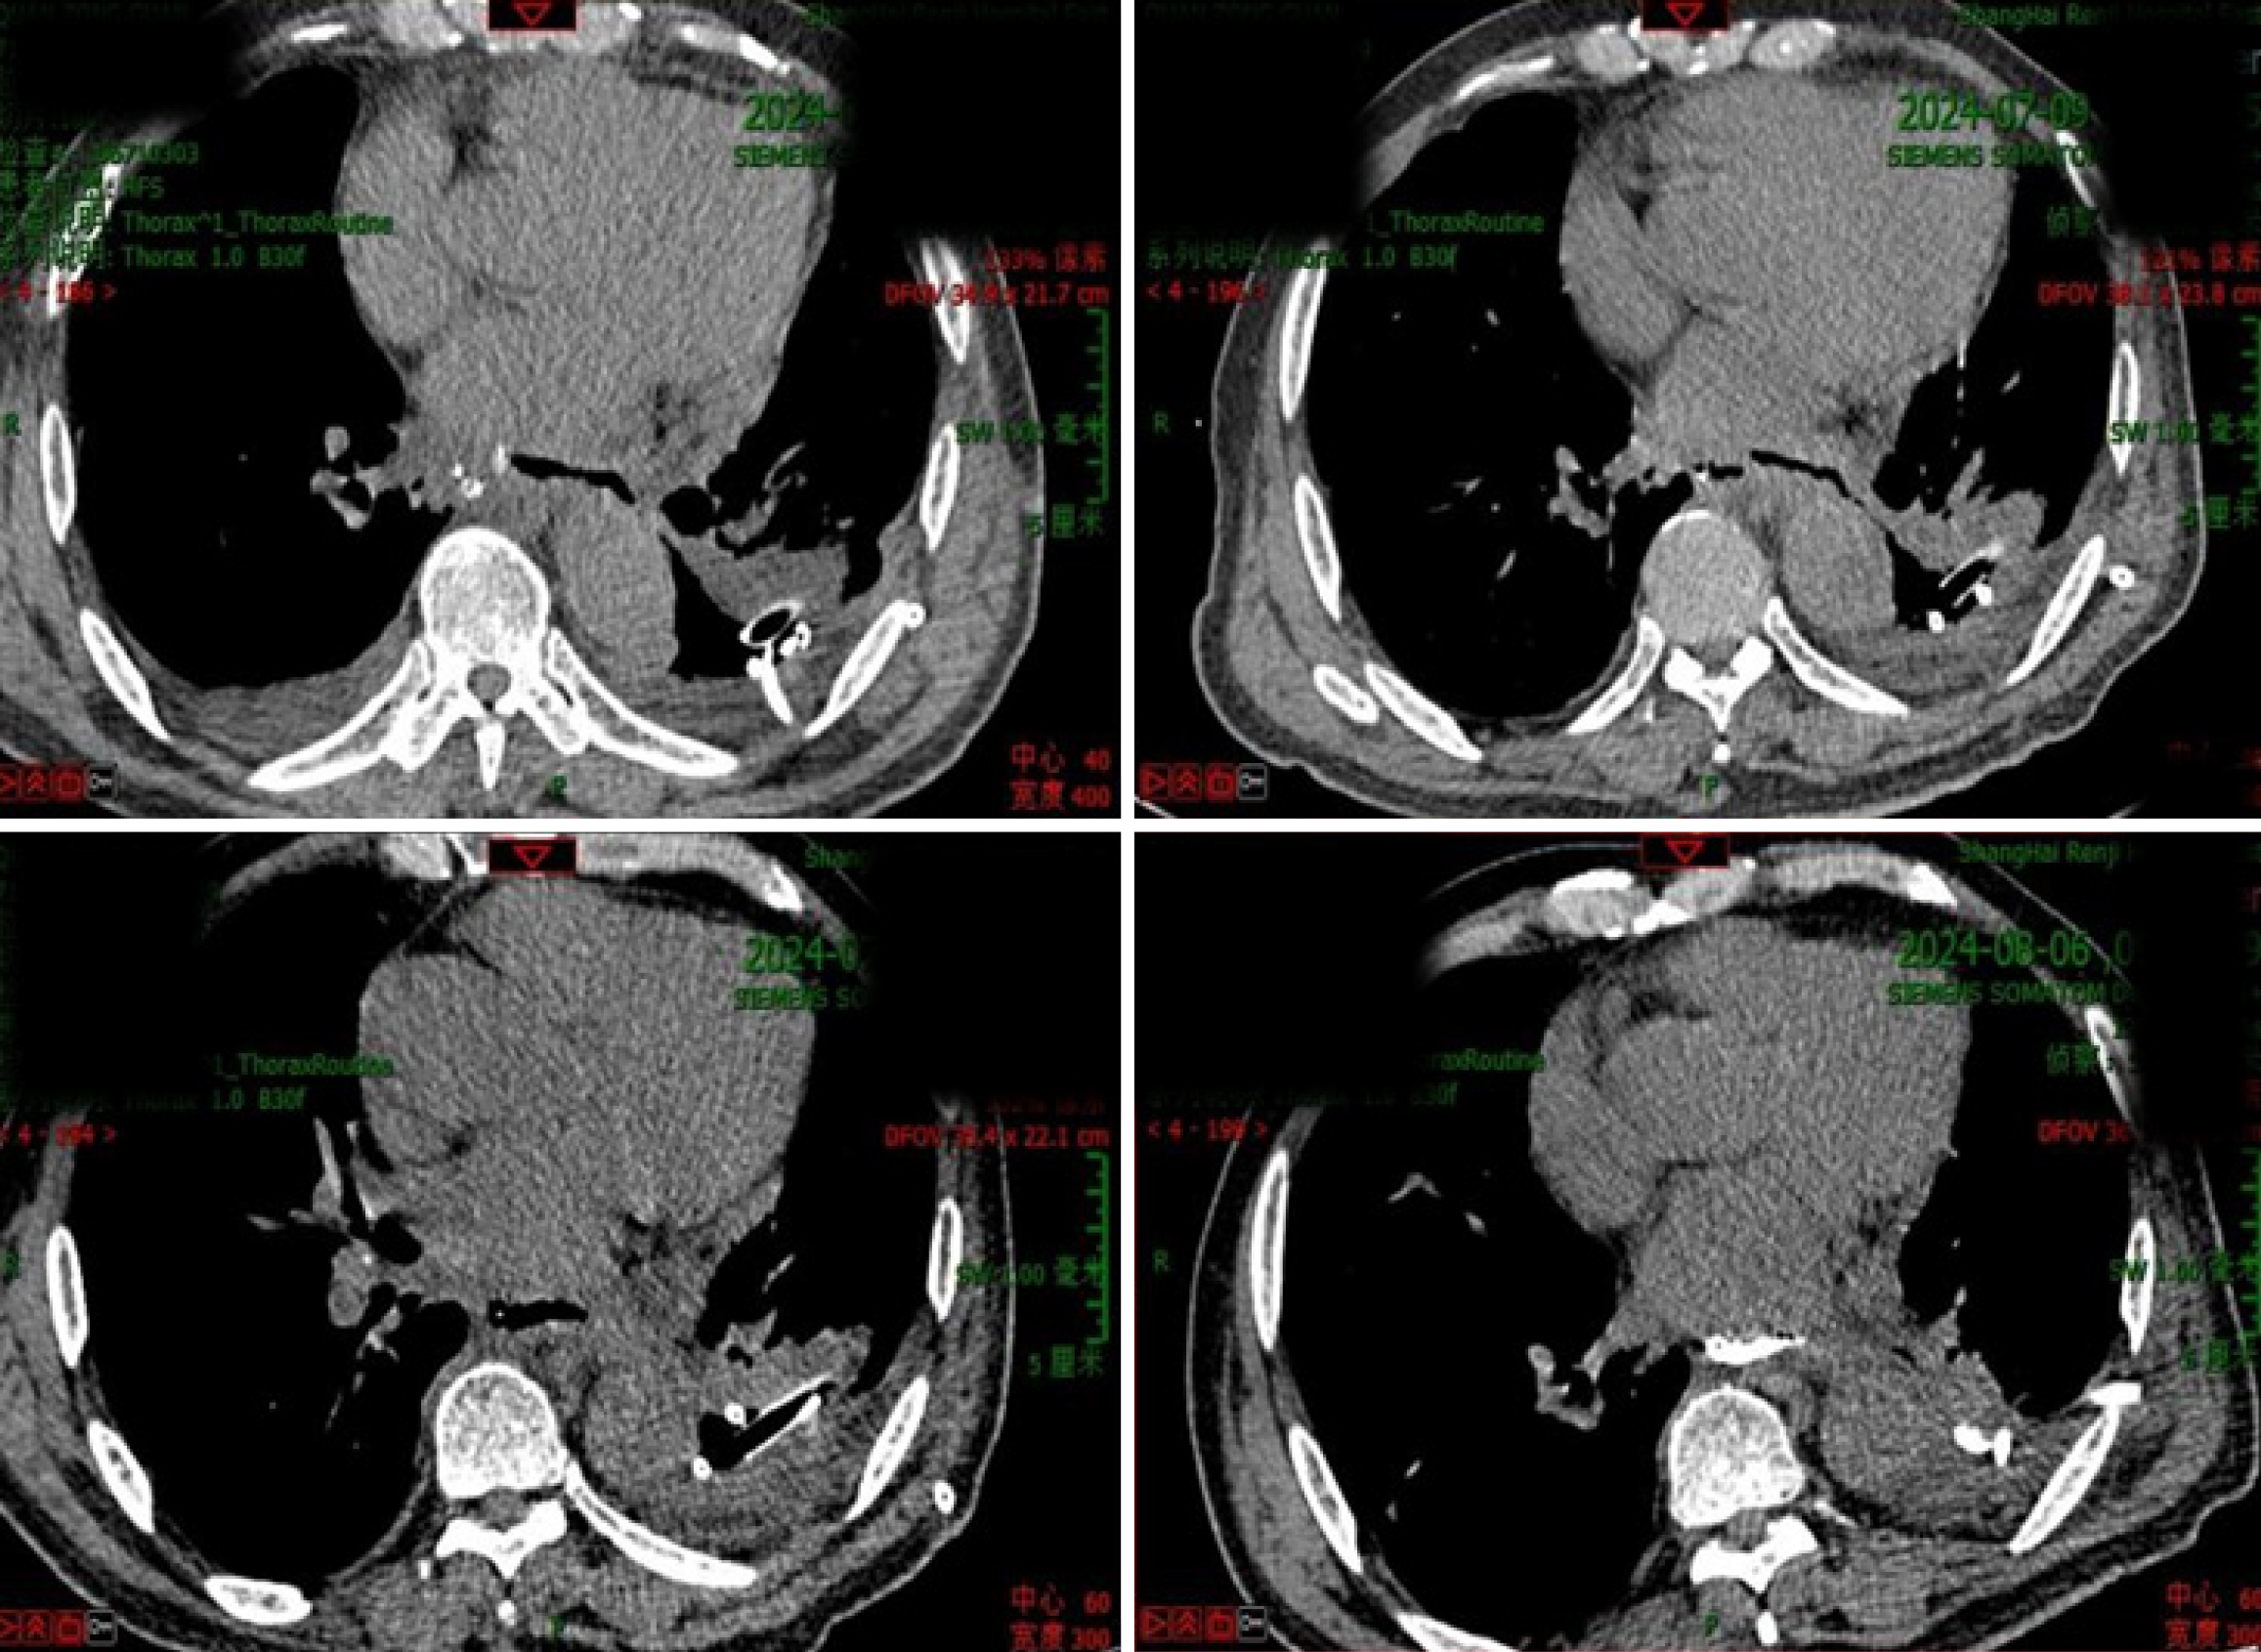

Figure 4 Computed tomography scan showing an esophageal fistula combined with mediastinitis and empyema.

Emergency debridement surgery was performed.

Figure 5 Computed tomography scans showing gradual healing of the fistula after emergency debridement surgery.